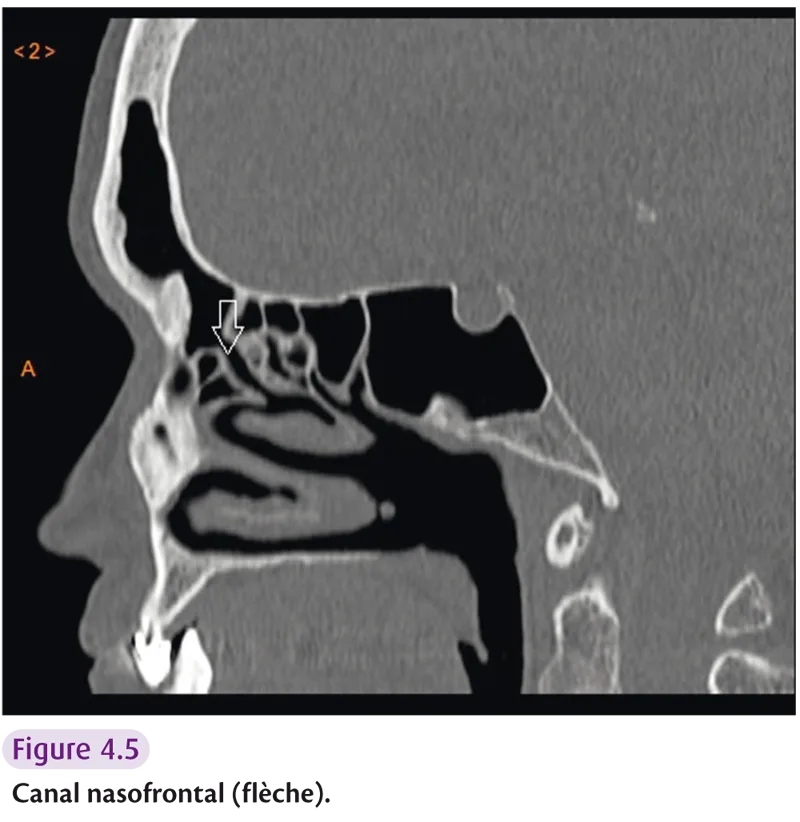

Sinus frontal

Ce sont des cavités creusées dans l’écaille frontale. Chaque sinus communique avec les fosses nasales par les canaux nasofrontaux et s’ouvre dans le méat moyen. Les cellules de l’agger nasise repèrent sur les coupes coronales en avant de la racine verticale des cornets moyens. Kuhn divise le système cellulaire fronto-ethmoïdal en six groupes : cellules de l’agger nasi, cellules supraorbitaires, cellules frontales, cellules de la bulle frontale, cellules suprabullaires et cellules de la cloison interseptale du sinus frontal.

L’anatomie radiologique comprend les trois cornets (inférieur, moyen et supérieur) et le vomer, os impair et médian participant à la constitution du septum nasal. Deux gouttières sont également décrites : l’infundibulum, extension supéro-interne de l’ostium du sinus maxillaire et le canal nasofrontal (figure 4.5). Ces gouttières s’ouvrent dans la gouttière uncibullaire (hiatus semi-lunaire) et rejoignent la gouttière rétrobullaire (sinus lateralis).

Fig 4.5